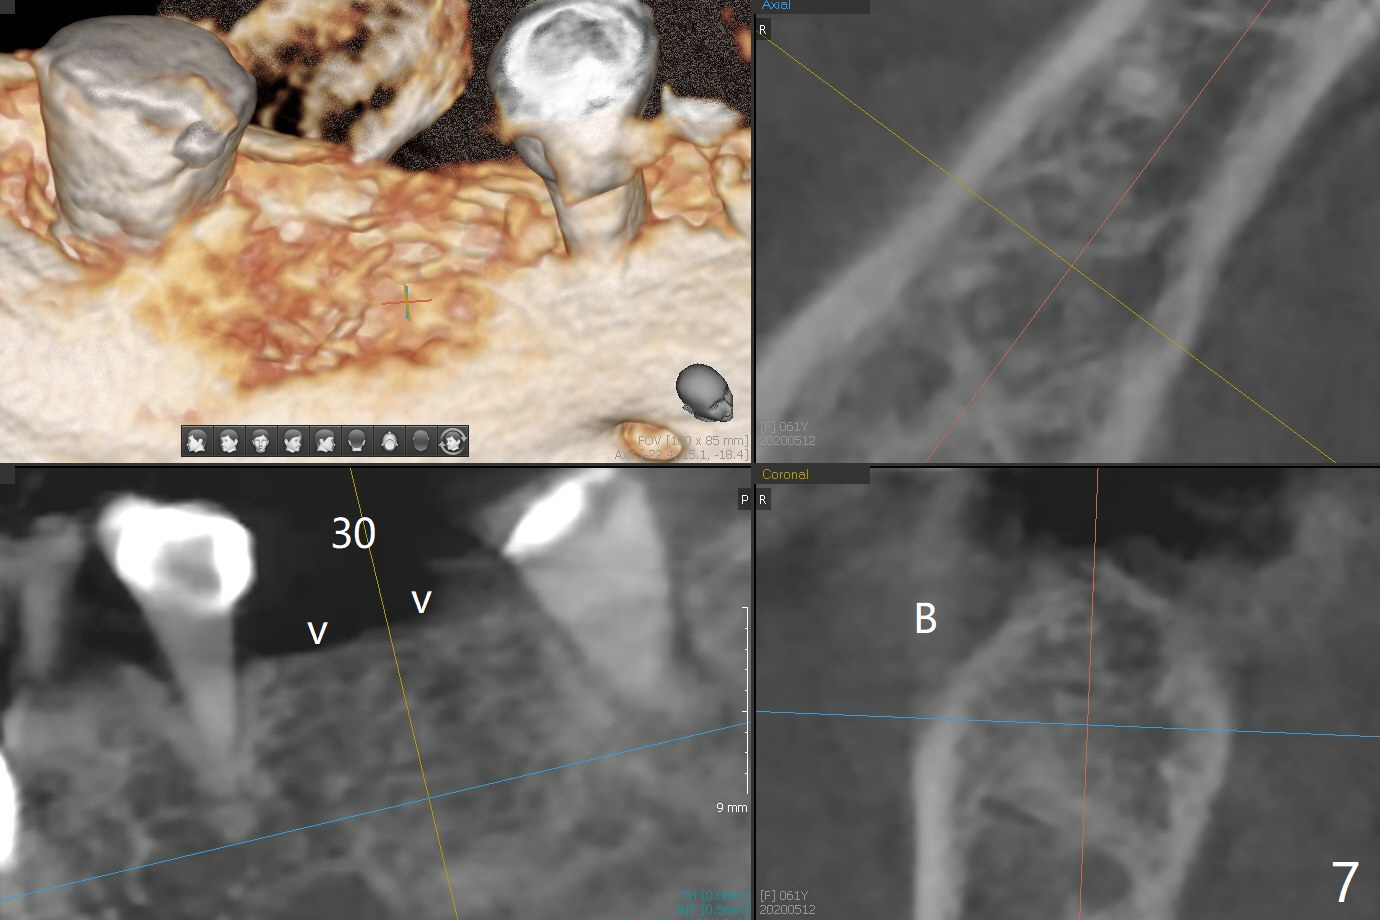

A 61-year-old woman with history of bruxism returns to clinic with chief complaint "I cannot chew bottom right. Top left has had pain and swelling before". Exam shows loose FPD at #31 (Fig.1) and necrosis of #14 (Fig.2). When the FPD is sectioned, the tooth #31 is found to have subgingival caries, filled with IRM (Fig.3). CT shows large PARL around MB and P roots of the tooth #14 (Fig.4), the fractured distal root of the tooth #19 with the low buccal plate (Fig.5) and a 5x10 mm implant being able to be placed at #30 (Fig.6). The crestal cortex (Fig.7 arrowheads) is thin in the edentulous area for several decades. The bone density is low (Fig.8, underprep). To place an implant over the pointed ridge, it should be trimmed prior to osteotomy (Fig.9). The bone loss associated with the fractured distal root is severe at #19 (Fig.10). After removal of the mesial root (Fig.11: 1), perform distal socket shield (2).